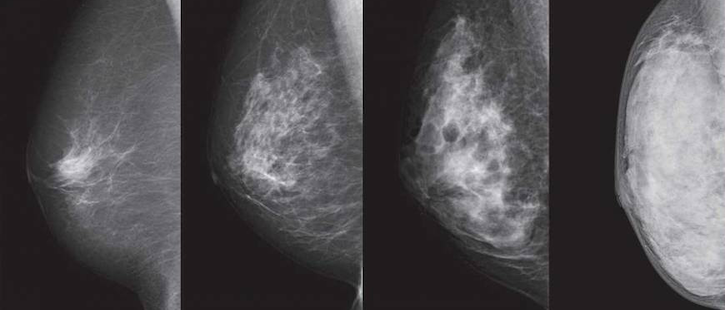

Deep Learning Model Predicts Risk of Breast Cancer Better than Traditional Practice

The model placed 31% of patients with future breast cancer in the top risk decile, versus the 18% seen with traditional models.

Photo/Thumb have been modified. Courtesy of NPO BREAST CANCER IMAGING NETWORK.

A deep learning model can be used to predict a woman’s future risk of breast cancer better than traditional practice, according to the findings of a study published in the journal Radiology.

The artificial intelligence (AI) model identified women at high risk for breast cancer and placed 31% of all patients with future breast cancer in the top risk decile. This was an improvement over the Tyrer-Cuzick model, which is typically used in clinical practice and was shown to predict risk in just 18% of patients.

Using a hybrid model, the researchers found that patients with non-dense breasts and model-assessed high risk had 3.9 times higher cancer incidence than patients with dense breasts and model-assessed low risk.

While AI models do not always perform well across diverse races, the hybrid model had an area under the curve of 0.71 for both Caucasian and African American women. The traditional model had an area under the curve of 0.62 and 0.45, respectively.

“Until now, African American women were at a distinct disadvantage in having accurate risk assessment of future breast cancer,” said Regina Barzilay, Ph.D., professor at the Massachusetts Institute of Technology (MIT).

Adam Yala, Ph.D. candidate at MIT, along with Barzilay and Constance Lehman, M.D., Ph.D., chief of breast imaging at Massachusetts General Hospital in Boston, compared three risk assessment models: One relied on traditional risk factors, one relied on deep learning that used the mammogram, and one hybrid approach incorporated traditional factors and mammograms. The team developed the models with risk factor information from patient questionnaires and electronic health records to assess breast cancer risks within five years.

Mammograms contain more information than just the four categories of breast density, Yala said. “So what (the model) will do is discover things that are subtle and might not be visible to the human eye, but are truly indicative of cancer risk,” he told Inside Digital Health™ in an interview.

The research team used nearly 89,000 full-resolution screening mammograms from more than 39,500 women between January 2009 and December 2012 to train, validate and test the model. The researchers obtained cancer outcomes through linkage to a regional tumor registry.

By identifying patients at risk early, there is an increased chance of survival due to early intervention.

“We can now leverage these kinds of models to do the discovery for us, and that results in much stronger tools,” Yala said.